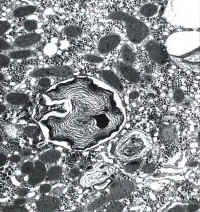

li-8-4-15.jpg (39589 bytes)

Fig. 8-4-15:

Mallory bodies

Fig. 8-4-17:

Myelin figures